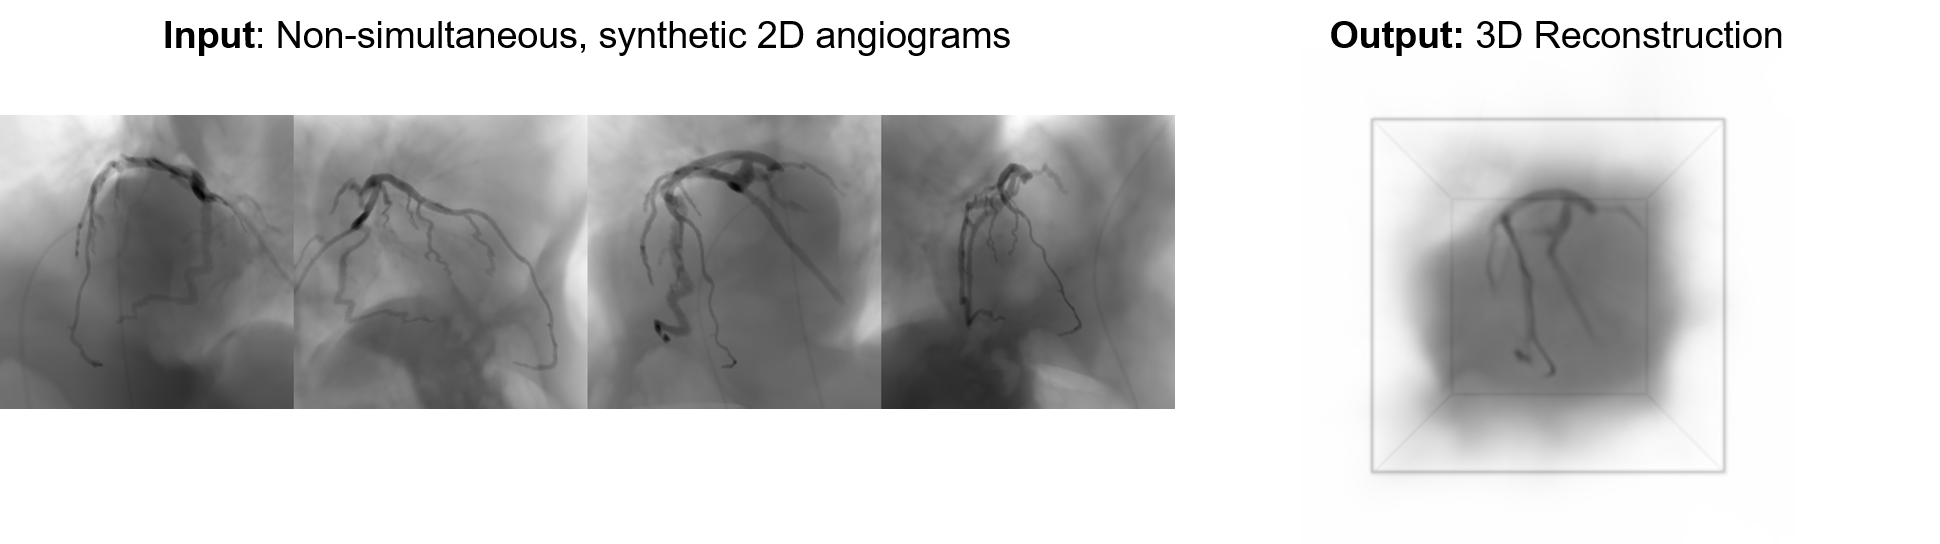

Toward Improved Non-Invasive Coronary Disease Assessment: 3D Coronary Reconstruction from X-Ray Angiography.

Wang LJ, Figueroa CA, Park JJ.

U.S. National Congress on Computational Mechanics 18 Chicago, Illinois, July 2025

We built a deep learning-based automated approach for reconstructing patient-specific 3D coronary trees from standard unsynchronized 2D angiogram videos, to enable downstream 3D quantitative analysis of coronary deformation and contrast washout dynamics. Our feed-forward transformer-based model reconstructs coronary radiodensity volumes from multiple sparse angiograms. We utilize a novel adversarial reconstruction loss, which enables robust supervision in the presence of uncertainty and inconsistency. Our model trains on unlabeled angiograms, allowing for improved scalability and generalizability in diverse clinical scenarios. Results suggest successful 3D coronary artery reconstruction from synthetic 2D angiograms.